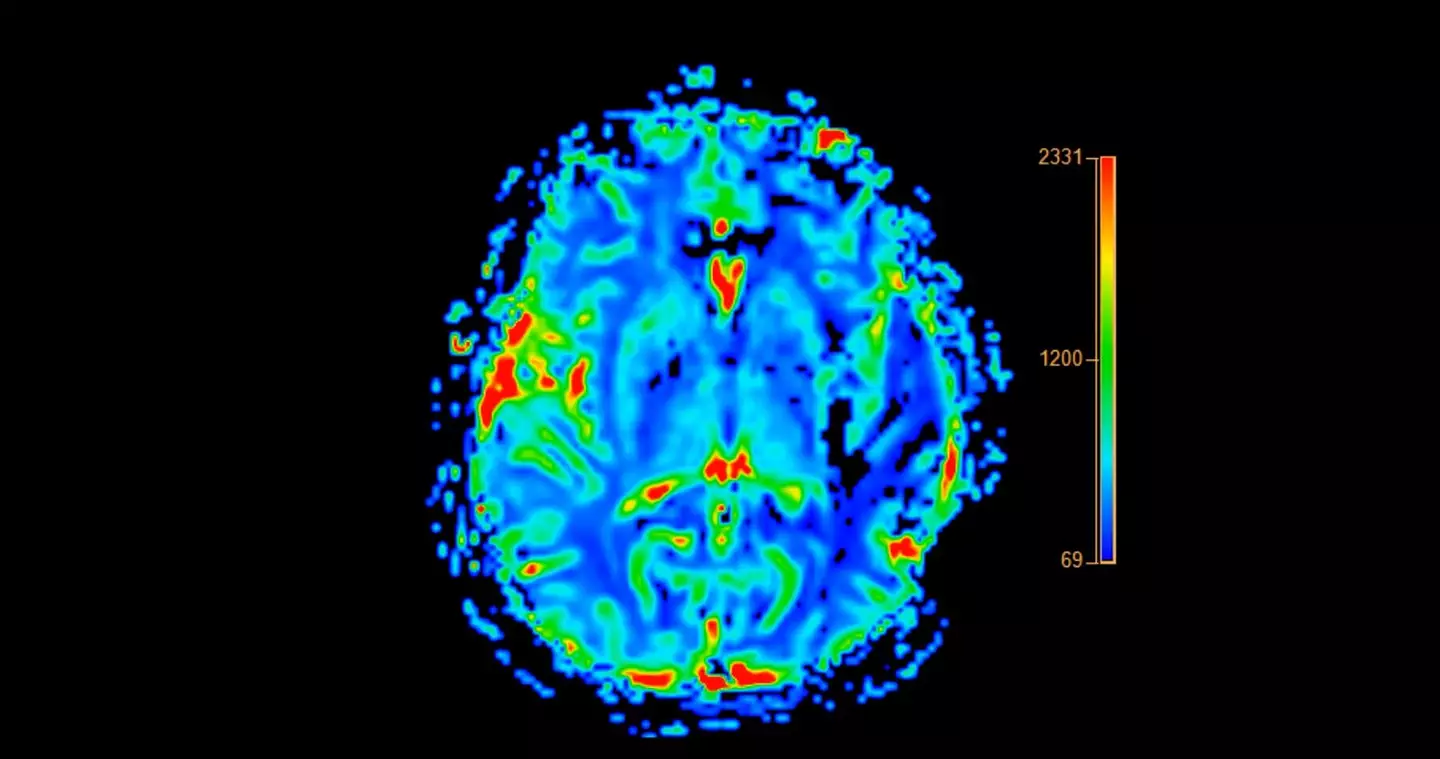

Doctors carried out extensive testing in order to establish what was causing these symptoms, and the 19-year-old patient was diagnosed with probable Alzheimer’s disease.